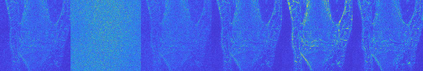

Magnetic Resonance Imaging (MRI) has excellent soft tissue contrast but is hindered by an inherently slow data acquisition process. Compressed sensing, which reconstructs sparse signals from incoherently sampled data, has been widely applied to accelerate MRI acquisitions. Compressed sensing MRI requires one or more model parameters to be tuned, which is usually done by hand, giving sub-optimal tuning in general. To address this issue, we build on previous work by the authors on the single-coil Variable Density Approximate Message Passing (VDAMP) algorithm, extending the framework to multiple receiver coils to propose the Parallel VDAMP (P-VDAMP) algorithm. For Bernoulli random variable density sampling, P-VDAMP obeys a "state evolution", where the intermediate per-iteration image estimate is distributed according to the ground truth corrupted by a zero-mean Gaussian vector with approximately known covariance. To our knowledge, P-VDAMP is the first algorithm for multi-coil MRI data that obeys a state evolution with accurately tracked parameters. We leverage state evolution to automatically tune sparse parameters on-the-fly with Stein's Unbiased Risk Estimate (SURE). P-VDAMP is evaluated on brain, knee and angiogram datasets and compared with four variants of the Fast Iterative Shrinkage-Thresholding algorithm (FISTA), including two tuning-free variants from the literature. The proposed method is found to have a similar reconstruction quality and time to convergence as FISTA with an optimally tuned sparse weighting and offers substantial robustness and reconstruction quality improvements over competing tuning-free methods.